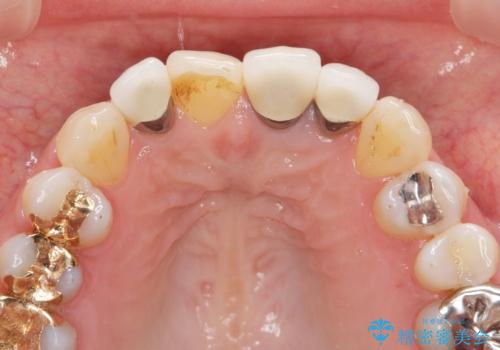

- 前歯のクラウンの歯肉の位置が年々変化し、歯ぐきのフチが黒くなってしまった、綺麗にしたいと希望されて来院されました。

装着されているセラミッククラウンを除去したのち、現在の歯ぐきのラインにしっかりと合う精度の高いオールセラミッククラウンを作製していきます。

- 39.6万円(ジルコニアクラウン×3・仮歯×3)費用は治療当時の料金となります